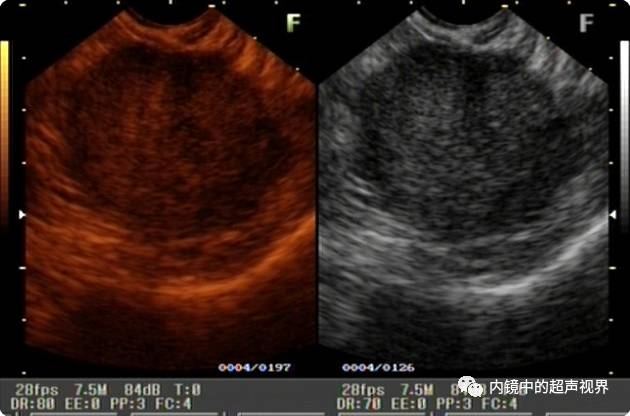

我现在使用的超声内镜DR可调节范围为30-90。以下三张图片显示的是同一个胰头肿物,肿物回声与胰腺回声非常接近,DR分别为90、70、40,其它参数相同,您更喜欢哪一张。

再来一纵隔肿物的图片,是DR30和80的对比,很明显。